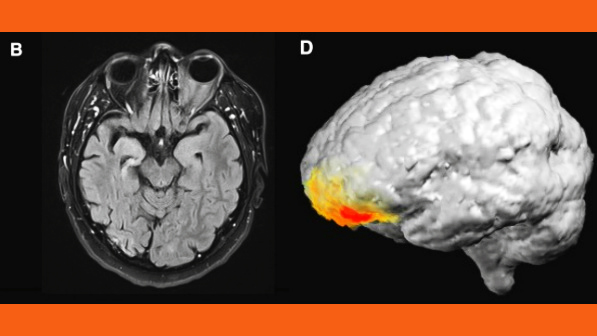

The researchers diagnosed the patient’s episode as “grandiose religious delusion of revelation and missionary zeal in the context of postictal psychosis (PIP).” They found an increase in activity in the low-gamma band (30–40 Hz) brain waves in the left prefrontal cortex of the patient’s brain, concluding “this suggests that religious conversion in PIP is related to control mechanisms in the prefrontal lobe-related processes rather than medial temporal lobe-related processes.” The same part of his brain that experienced epileptic seizures lit up, as seen here: